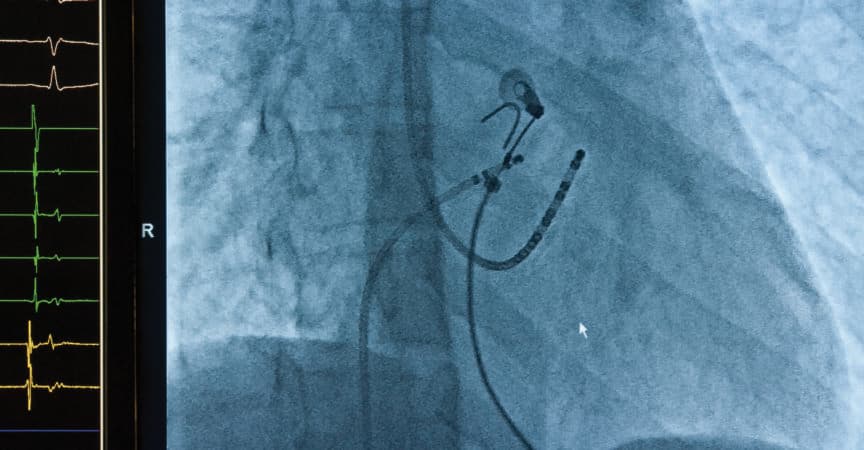

Die Studienergebnisse sprechen für eine frühe Rhythmuskontrolle, zum Beispiel durch eine Katheterablation.

Über viele Jahre hatte sich die kardiologische Community daran gewöhnt, beim Vorhofflimmern Frequenzkontrolle vor Rhythmuskontrolle zu stellen. Jetzt scheint sich das zu ändern.